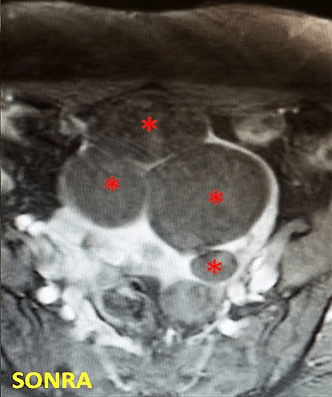

32 yaşında, adet kanamalarında artma ve kansızlık şikayetleri mevcut. Emar’da 2 adet intramural miyom (*) izleniyor. Miyomektomi önerilmiş, ancak gerekirse rahimin alınabileceği söylenmiş. Embolizasyondan sonra miyomların öldüğü ve küçüldüğü izleniyor. İşlemden 2 ay sonra hastanın adetleri normalleşmiştir.